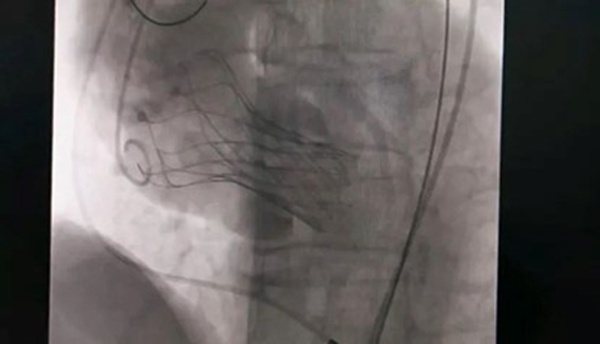

专家联合会诊。重庆西区医院供图10月18日,该患者实施手术,在新桥医院专家的指导下,心血管内科主任宋明宝带领团队把瓣膜置入心脏。

人工瓣膜置入中。重庆西区医院供图宋明宝介绍,正常情况下,主动脉瓣完全打开后,瓣口面积在3-4平方厘米,如果瓣口面积在1平方厘米以下,则为重度狭窄,而该患者的瓣口面积仅0.51平方厘米。主动脉瓣不能完全打开,好比“心脏阀门”活动不畅,血液不能顺畅进入主动脉。为适应这一变化,患者左心室不断增大收缩压力,导致左心室不断扩大,心脏功能衰竭,随时有猝死可能。术后,患者状态良好,达到治疗预期。(重庆西区医院 供稿)